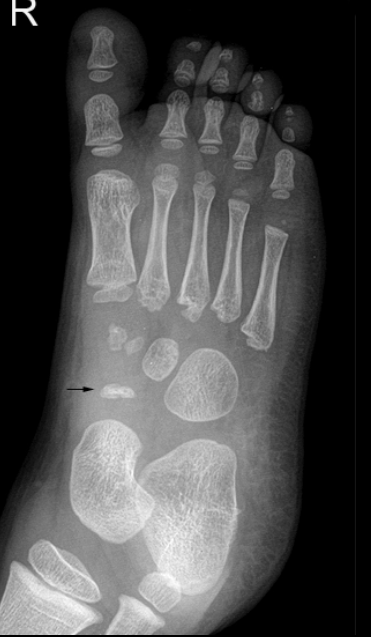

What bone is affected in Freiberg’s disease?

Metatarsal head, usually 2nd (80%), sometimes 3rd.

Who is most affected by Freiberg’s disease?

Teen females (5:1), athletes, high-heel wearers.

Pathogenesis of Freiberg’s disease?

Repeated stress → microfractures at growth plate → necrosis → deformity.

Symptoms of Freiberg’s disease?

Localized forefoot pain, tenderness, worsens with activity.

Radiographic appearance of Freiberg’s disease?

Early: cortex collapse, sclerosis, altered joint space. Late: enlarged, fragmented head.

Treatments for Freiberg’s disease?

Reduced activity, casting, or surgery (excision, transplant).

What bone is affected in Köhler’s disease?

Navicular bone (foot).

Typical age group for Köhler’s disease?

Children 3–7, mainly boys.

Signs & symptoms of Köhler’s disease?

Midfoot pain/swelling, limping with weight shifted laterally.

Radiographic findings in Köhler’s disease?

Patchy/homogeneous sclerosis, collapse/fragmentation, eventual revascularization with abnormal shape.

Treatments for Köhler’s disease?

Pain relief, 6–8 weeks casting, arch supports; resolves with time.